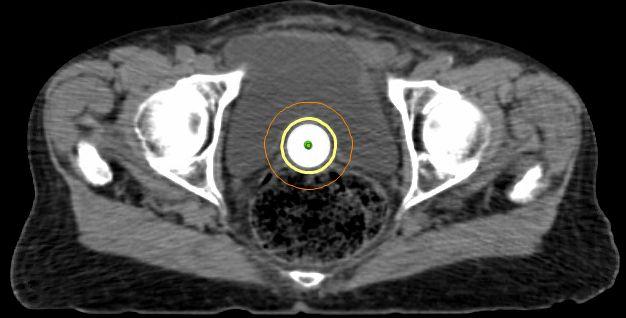

Brachytherapy (“short” in Greek)

• Intracavitary – Breast, Cervix, Endometrium

• Interstitial – Prostate, Lip, Sarcoma, Breast, Vagina

Brachytherapy - Cylinder

•Treats vaginal cuff only (most common site of recurrence in intermediate risk)

•1-2x per week for 3 weeks

•Intermediate risk patients

• Brachytherapy

• Total dose: 21-30 Gy

• 4-7 Gy, 1-2x per week

• 3-6 treatments over 3 weeks

Simulation

• CT scan

• Immobilization device

• Draw tumor and normal structures on CT slice-by-slice (“contouring”)

• Entire treatment based on this CT scan